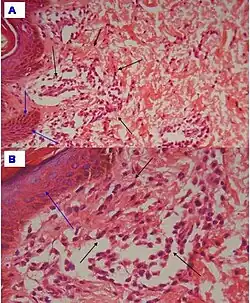

| Urticaria, lymphocyte predominant | Perivascular location. Mast cells are relatively sparse, potentially demonstrated with special stains, preferably tryptase stain. Extravasated erythrocytes are present in about 50% of the cases. No vasculitis.[14] | Dermal edema [solid arrows in (A,B)] and a sparse superficial predominantly perivascular and interstitial infiltrate of lymphocytes and eosinophils without signs of vasculitis (dashed arrow).[15]

|

| Urticaria, lymphocyte predominant | Perivascular location. Mast cells are relatively sparse, potentially demonstrated with special stains, preferably tryptase stain. Extravasated erythrocytes are present in about 50% of the cases. No vasculitis.[14] | Dermal edema (solid arrows) and a sparse superficial predominantly perivascular and interstitial infiltrate of lymphocytes and eosinophils (dashed arrow)

| Prevesicular stage of bullous pemphigoid | Image at right shows influx of inflammatory cells including eosinophils and neutrophils in the dermis (solid arrow) and blister cavity (dashed arrows), and deposition of fibrin (asterisks).[15] However, the diagnosis of bullous pemphigoid consist of at least 2 positive results out of 3 criteria:[19]